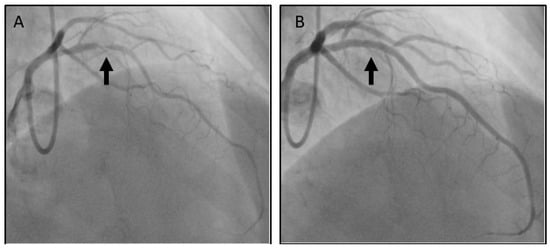

2. Case Presentation